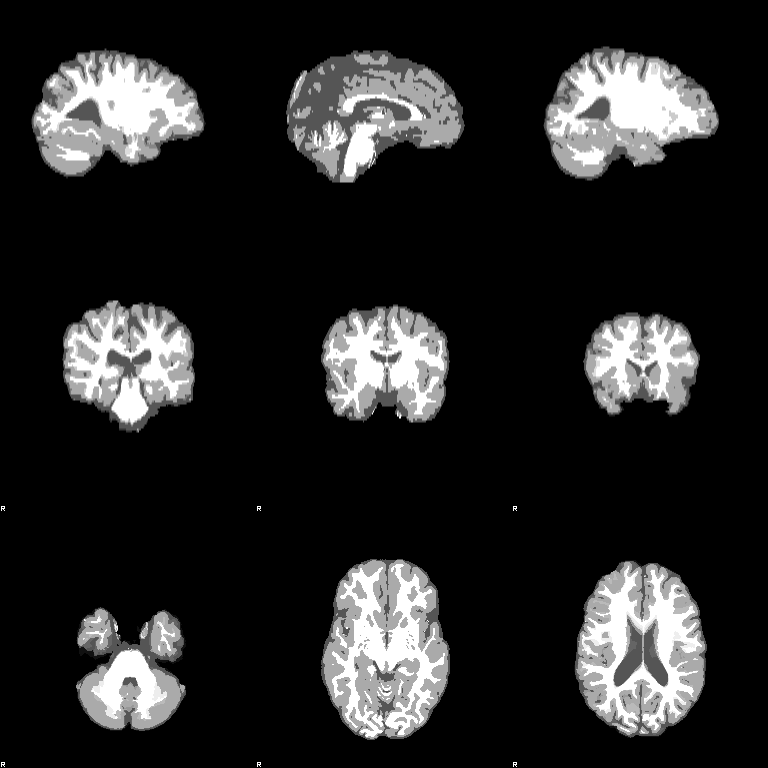

FAST

Set the Input image to be structural_brain (i.e. it is important to have run BET first). Turn on the Partial volume maps optional output images. Press Go. The outputs will be structural_brain_seg, structural_brain_pve_0, structural_brain_pve_1 and structural_brain_pve_2.